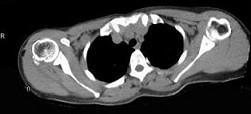

女,47岁,右肩部疼痛并肩关节活动受限数月,请结合所提供的图像,选择最佳选项 ( )A、未见明显异常B、肩周炎C、颈部肿瘤D、...

问题 女,47岁,右肩部疼痛并肩关节活动受限数月,请结合所提供的图像,选择最佳选项 ( )

选项 A、未见明显异常 B、肩周炎 C、颈部肿瘤 D、化脓性肩关节炎 E、颈椎病

答案 B